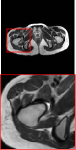

Figure 5 provides the qualitative comparison of the various methods on the four datasets at a scale of 4. The top, second, third, and bottom rows are the SR results under the FastMRI, clinical brain, clinical tumor and clinical pelvic datasets, respectively. The red boxes indicate the zoom-in region of complicated anatomical structures along with their corresponding error maps. Note that the brighter textures in the error maps, the lower the quality of the reconstructed images. As can be seen, compared to methods based on Transformers and CNNs, diffusion-based methods like DisC-Diff and DiffMSR (Ours) are capable of reconstructing high-realistic images with promising reconstruction metric scores (PSNR and SSIM). Nevertheless, while DisC-Diff can reconstruct high-precision MR images, it does not preserve the structure present in the original HR images, introducing some additional information that can affect medical diagnosis. In contrast, our method combines DM and PLWformer, which can preserve the original image’s structure while restoring high-frequency information.

In this section, we present more visual qualitative comparisons. Figures 8, 9, 10, and 11 show the reconstruction results of each method in FastMRI, clinical brain, clinical tumor, and clinical pelvic, respectively. As can be seen, although DisC-Diff can reconstruct MR images with high-frequency information, it fails to preserve the structure and content of the original Target HR image effectively, resulting in image distortion. In contrast, our proposed DiffMSR can restore high-frequency information while preserving the structure of the original HR image, indicating the effectiveness of the joint use of DM and PLWformer.